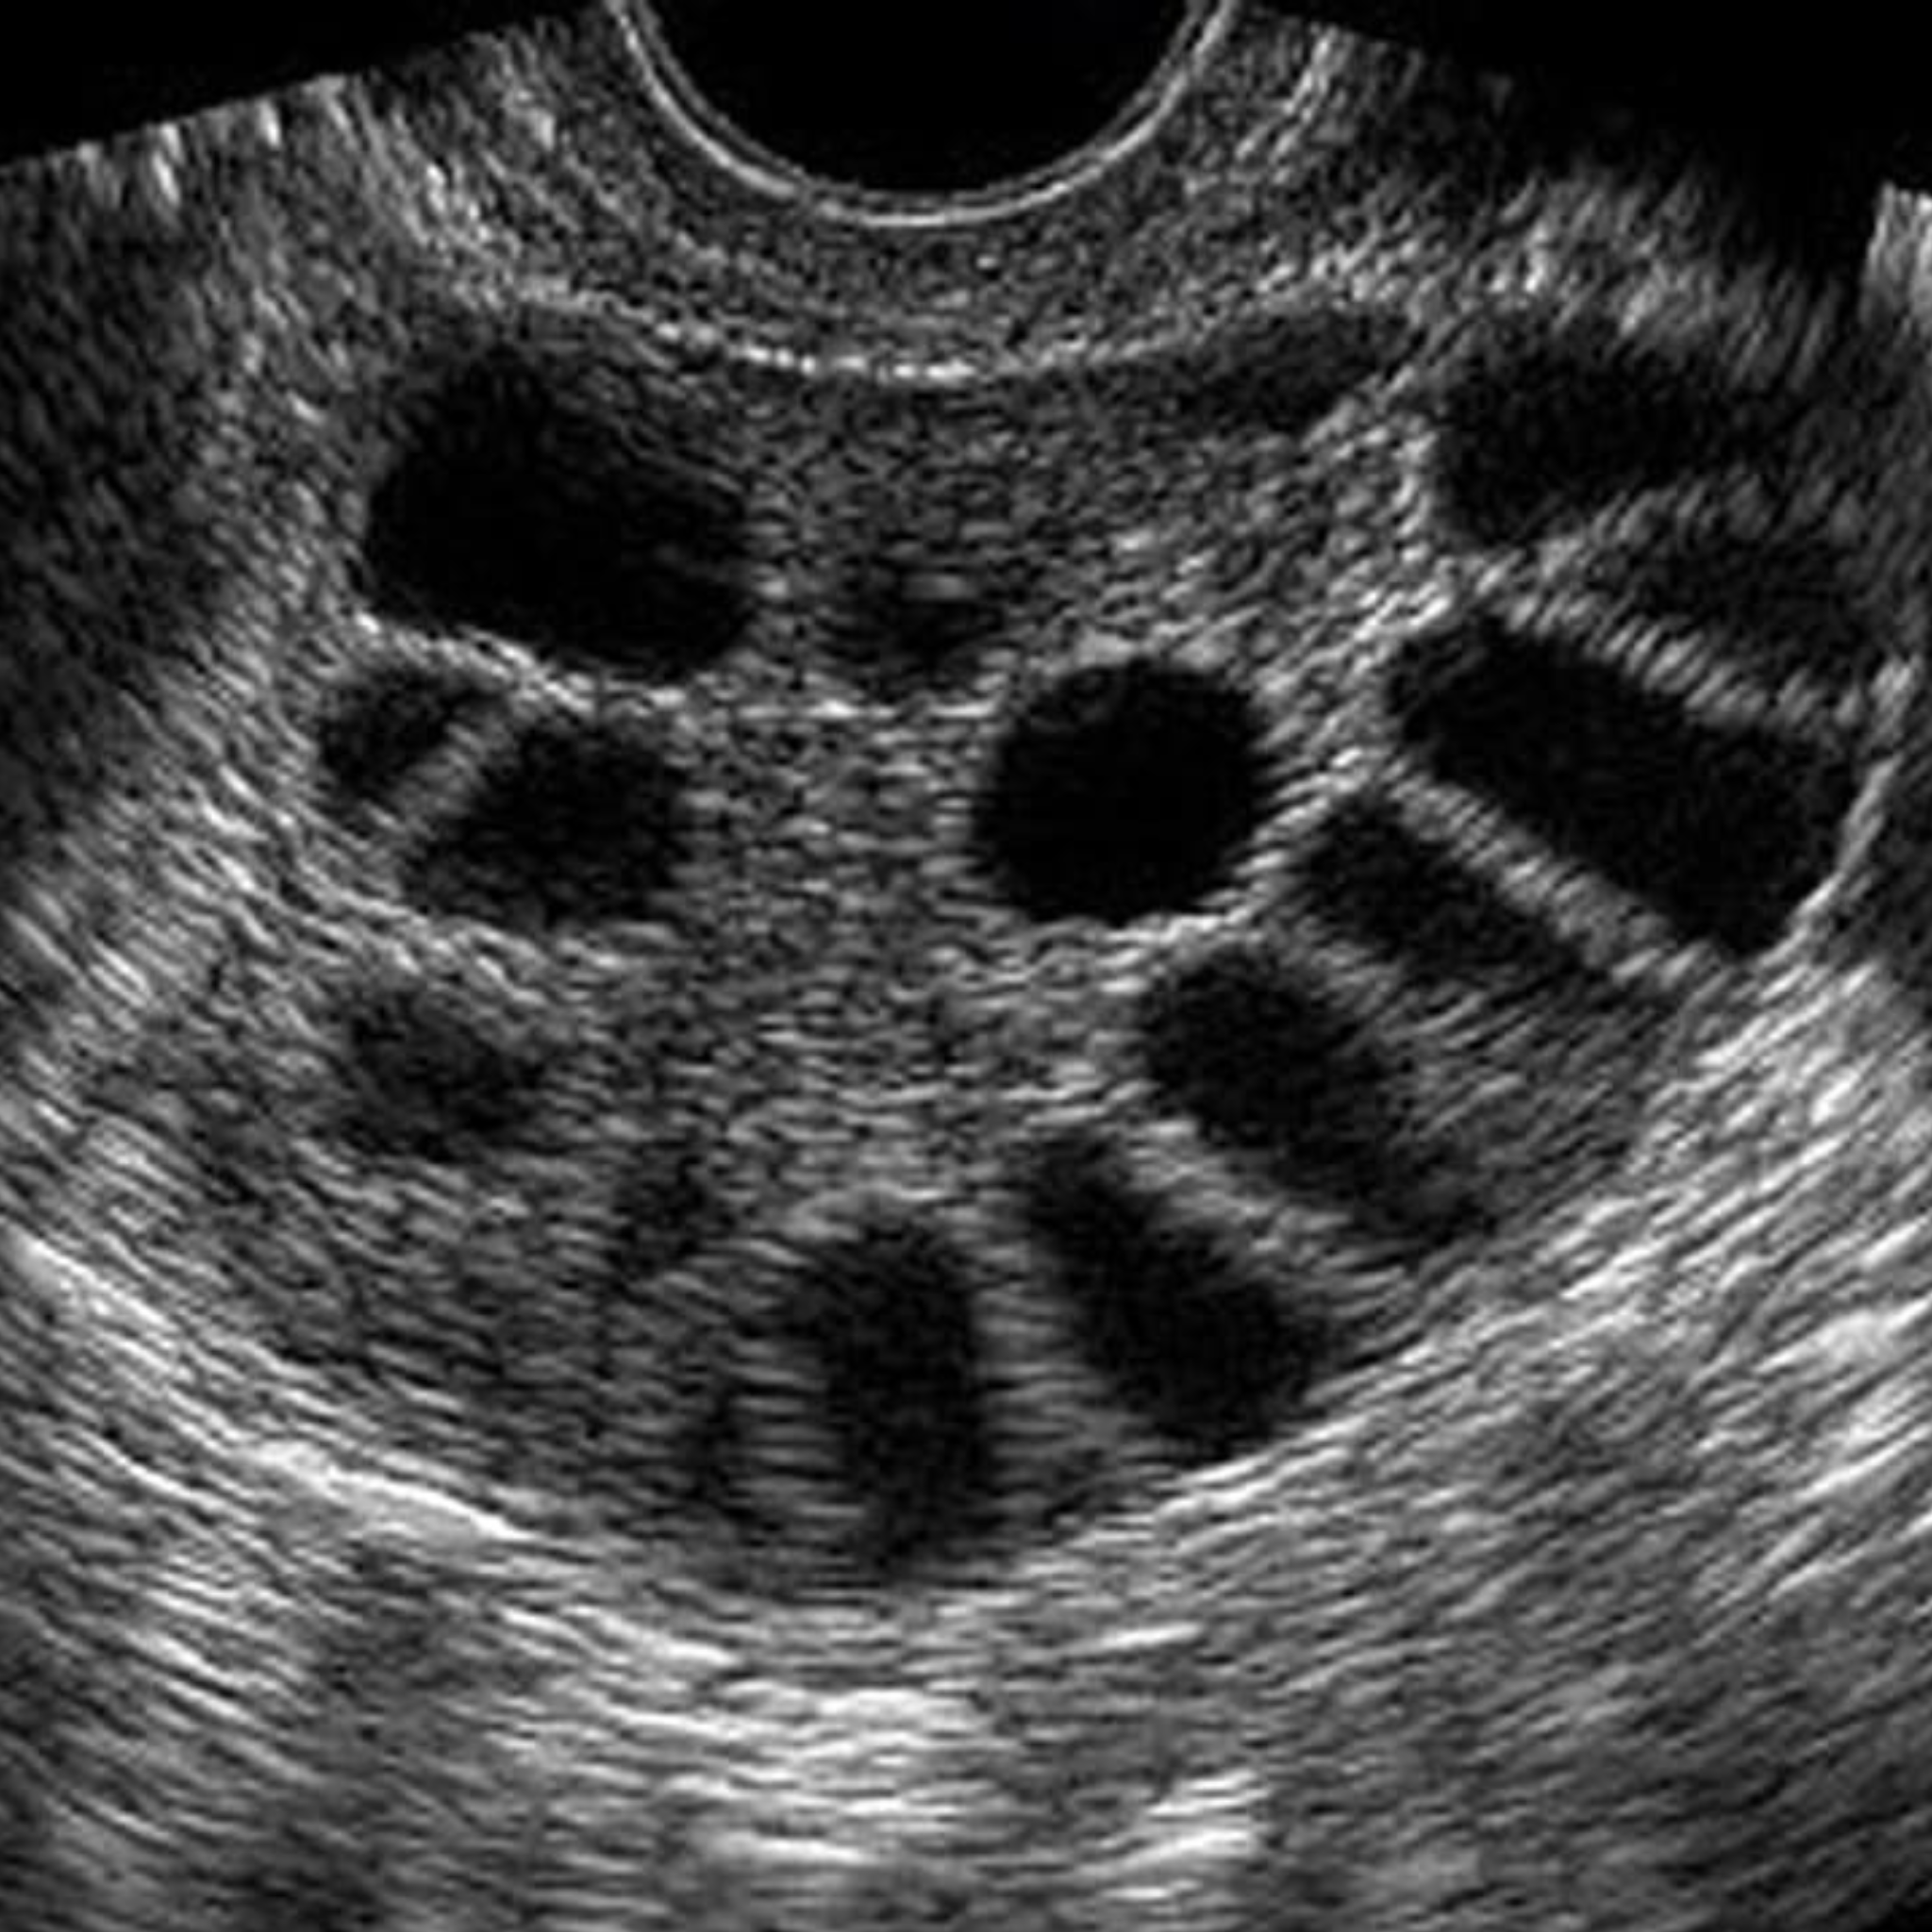

Phương pháp thường được dùng là chọc hút noãn dưới sự hướng dẫn của siêu âm ngã âm đạo. Khi đầu dò được đưa vào âm đạo để xác định vị trí nang noãn, một kim nhỏ được đưa xuyên qua thành âm đạo, tới nang noãn và chọc hút lấy noãn.

Noãn được lấy ra khỏi nang noãn bằng kim, kết nối với máy hút. Nhiều noãn có thể được chọc hút và thủ thuật kéo dài khoảng 15-30 phút, tuỳ số nang noãn trên siêu âm.